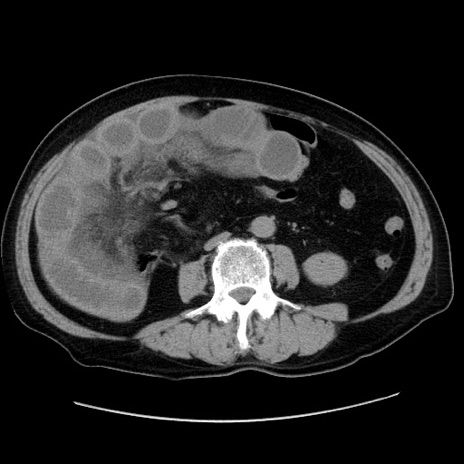

症例30(横断像)

【症例】80歳代男性

【主訴】臍周囲痛

【現病歴】約6時間前から臍下部痛が出現。次第に腹部膨隆・背部痛も生じてきたため来院。背部痛の場所は変化しない。

【既往歴】腎盂腎炎

【身体所見】意識清明、BT 36.3℃、BP  131/87mmHg、P 87bpm、SpO2 100%(RA)、臍周囲自発痛・圧痛あり、反跳痛なし、自発痛部位に一致して板状硬あり、腹部膨隆、腸雑音減弱、CVA tenderness両側陰性。

【データ】WBC 19600、CRP 0.33